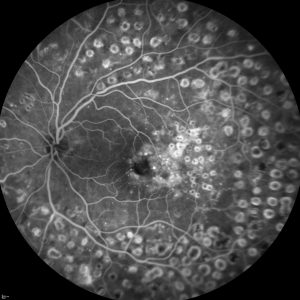

A personas que presenten Edema Macular Diabético y que aún no han recibido tratamiento previo específico para dicha patología. Una vez evaluado el caso, desde la Unidad de Retina y Vítreo del Hospital La Arruzafa explicará al paciente el estudio y se evaluará si cumple con todos los requisitos para poder entrar en el ensayo.

Se trata de un ensayo clínico desarrollado en varios centros a nivel internacional que evalúa la eficacia y seguridad del fármaco en investigación, en comparación con otro tratamiento ya existente. Su duración es de 1 año.

Evaluar la eficacia y seguridad de un medicamento en investigación en comparación con uno de los tratamientos actuales.